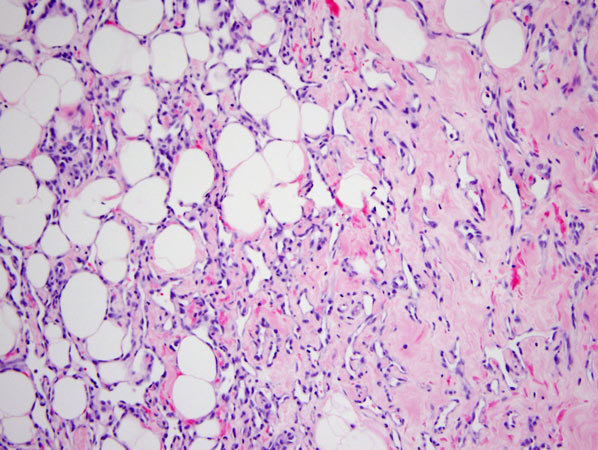

Microglandular adenosis

Histology?